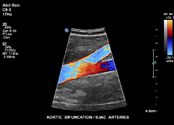

vaskular.pdf